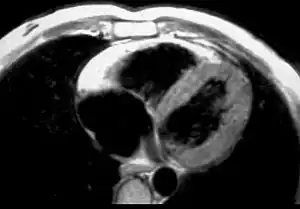

MRI in a patient affected by ARVC/D (long axis view of the right ventricle): note the transmural diffuse bright signal in the RV free wall on spin echo T1 (a) due to massive myocardial atrophy with fatty replacement (b).

In vitro MRI and corresponding cross section of the heart in ARVD show RV dilatation with anterior and posterior aneurysms (17-year-old asymptomatic male athlete who died suddenly during a soccer game).